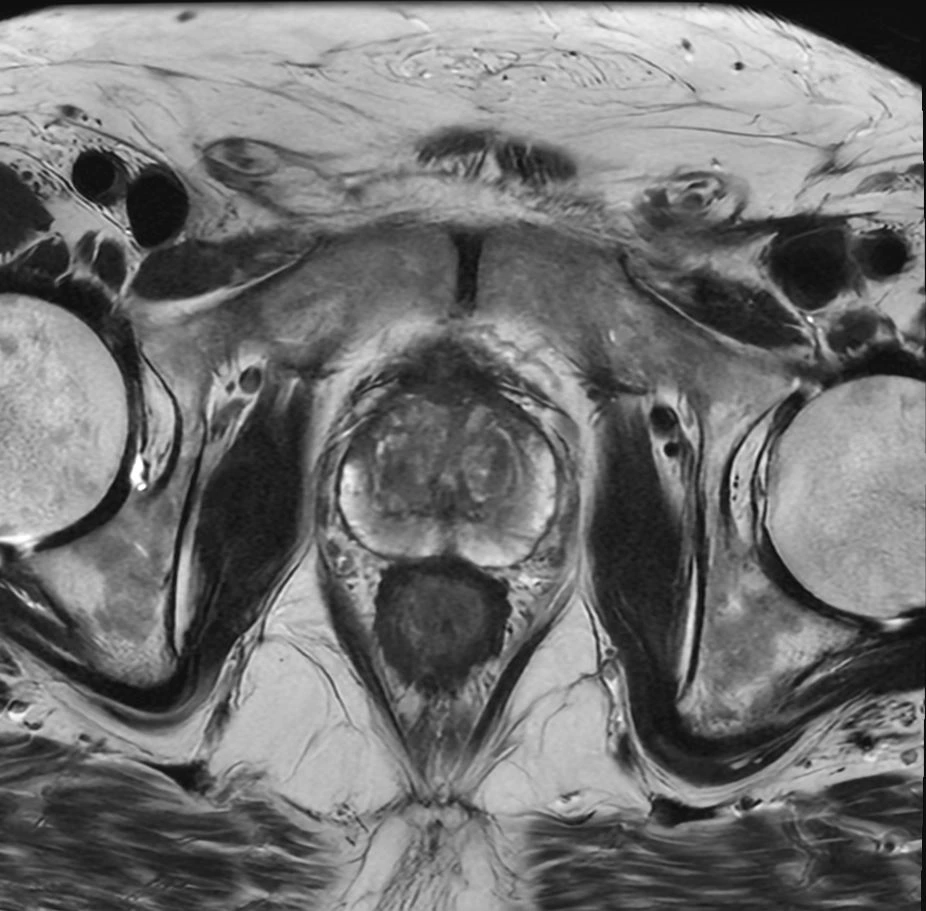

Eksempler på MR Scanninger

En MR-scanning af prostata er en skånsom undersøgelse, der giver meget detaljerede billeder af din prostatakirtel. Vores 3 tesla MR-scanner bruger et kraftigt magnetfelt og radiobølger til at skabe præcise billeder – helt uden brug af røntgenstråling.

Ved undersøgelsen får du en kontrastvæske, som sprøjtes ind i en blodåre. Kontrasten hjælper vores radiologer med at skelne mellem normalt prostatavæv og eventuelle sygdomsforandringer. Dette følger de gældende retningslinjer og giver langt mere pålidelige resultater end ældre undersøgelsesmetoder.

MR-scanningen kan vise forandringer i prostata, som hverken kan mærkes ved fysisk undersøgelse, ses på ultralyd eller opdages gennem en PSA-blodprøve. Denne høje præcision betyder, at undersøgelsen kan afklare, om der overhovedet er grund til at tage vævsprøver (biopsier).